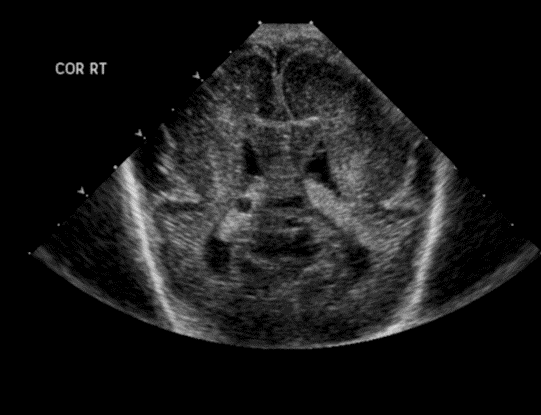

CSF spaces/ventricular system

There is prominence of the ventricular system. [Yes/No]

There is an asymmetry of the ventricular system. [Yes/No]

The lateral ventricle/s are dilated. [Yes/No]

The third ventricle is dilated. [Yes/No]

The 4th ventricle is dilated. [Yes/No]